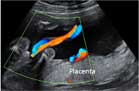

La imagen de la ecografía en 4D ha captado a este feto de 19 semanas de gestación moviendo sin parar sus brazos y piernas. Sus extremidades inferiores y superiores ya tienen una longitud acorde al resto de su cuerpo.

En este vídeo podemos apreciar a un bebé de 19 semanas con todos los miembros en activo, imágenes muy apreciadas por los especialistas. Junto al movimiento de brazos y piernas, se aprecia perfectamente el cordón umbilical.